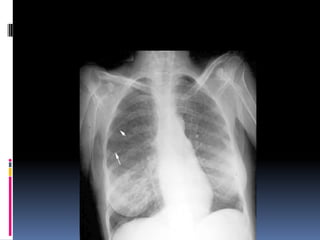

Cannon ball appearance- DDS

Osteogenic sarcoma

Thyroid (follicular)

Testicular carcinoma

Kidney

Choriocarcinoma

Prostate

Malignant melanoma,       Some GI,    Some very

advanced      nasopharyngeal, and    pharyngeal

carcinomas

Breast

Lymphangitis carcinomatosa

Cannon ball appearance-DDS Osteogenic sarcoma Thyroid (follicular) Testicular carcinoma Kidney Choriocarcinoma Prostate Malignant melanoma, Some GI, Some very advanced nasopharyngeal, and pharyngeal carcinomas Breast Lymphangitis carcinomatosa